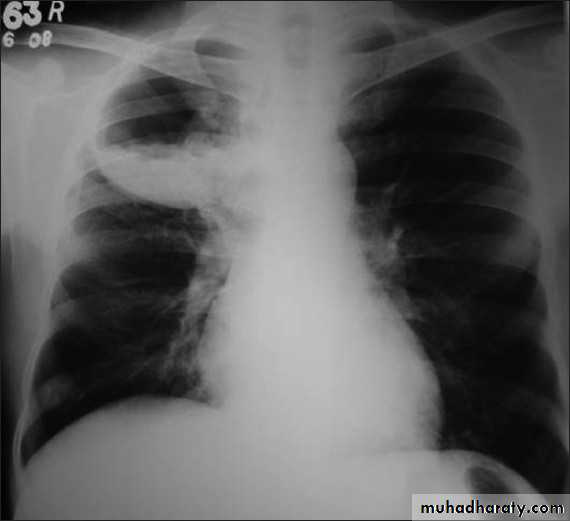

Right middle lobe collapse has distinctive features, and is usually relatively easily identified.

Radiographic features

Chest radiograph

Frontal chest XR showing opasity cause obscuration of the RT cardiac border

Lateral chest XR film the opacity is tongue like shape

versus (triangular in shape) in RT middle lobe consolidation seen in lateral chest XR film

RT lower lobe collapse

usually the medial aspect of the dome of right hemidiaphragm is lost.

the right hilum is depressed

It is important to note that the right heart border, which is contacted by the right middle lobe remains well seen.

Non-specific signs indicating right sided atelectasis may also be present (although due to the small size of the right middle lobe they may well be subtle). They include:

elevation of the hemidiaphragm

crowding of the right sided ribs

shift of the mediastinum to the right